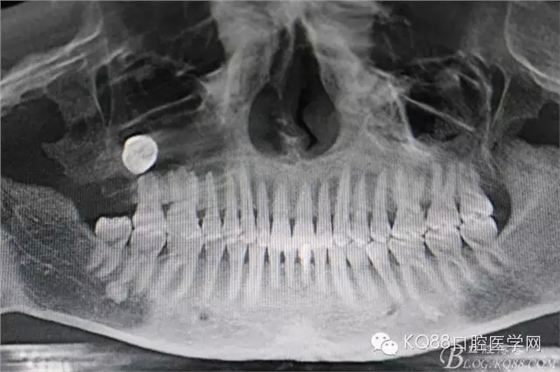

圖2.術(shù)前做全景片影像檢查:18頰舌向高位阻生,牙冠位于17牙根的正上方,懷疑18位于上頜竇內(nèi)。